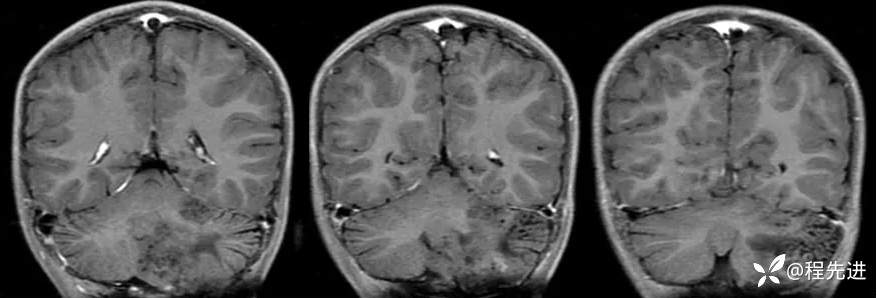

【患者信息】:男,6岁

【主诉】:查体发现左侧小脑半球占位3个月

【现病史及既往史】:患者3个月前因鼻塞至外院就诊,行头颅CT检查偶然发现颅内占位

【检查】